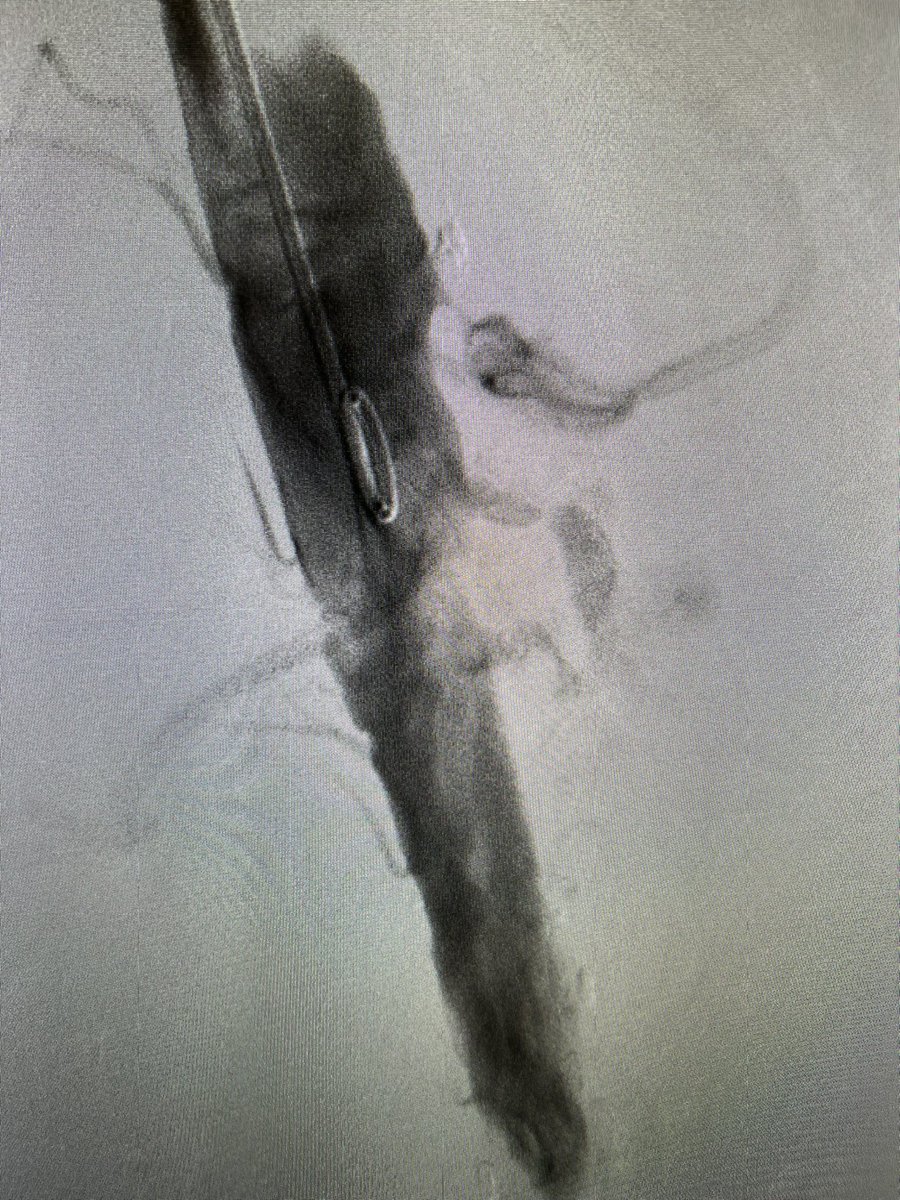

FEVAR with Diameter Reducing Ties plus 4 preloaded through-and-through wires for a small lumen case. Access from above. #AortaEd @gracemulatti @paulomenezesf @cfbechara @fonseca_alan5 @AndrePoci